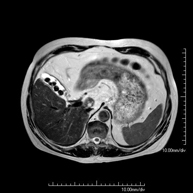

Prueba diagnóstica no invasiva que consiste en la obtención de imágenes de alta definición anatómica del abdomen mediante el empleo de un campo electromagnético y ondas de radio (con un emisor y un receptor). No utiliza radiación ionizante. En esta exploración se incluyen el hígado, páncreas, bazo, vía biliar, vesícula biliar,Entero-RM glándulas suprarrenales, riñones, aorta abdominal, vena cava inferior, estómago, duodeno,…En ocasiones se deberá emplear contraste paramagnético (Gadolinio) para caracterizar las lesiones. - RM Pelvis femenina